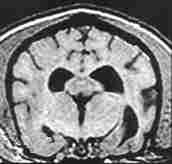

El Síndrome de Disfunción Cognitiva en perros se produce como resultado del envejecimiento del cerebro.

Este envejecimiento puede provocar cambios fisiológicos, como la acumulación de proteínas en el cerebro, que pueden afectar a la función cognitiva del perro.